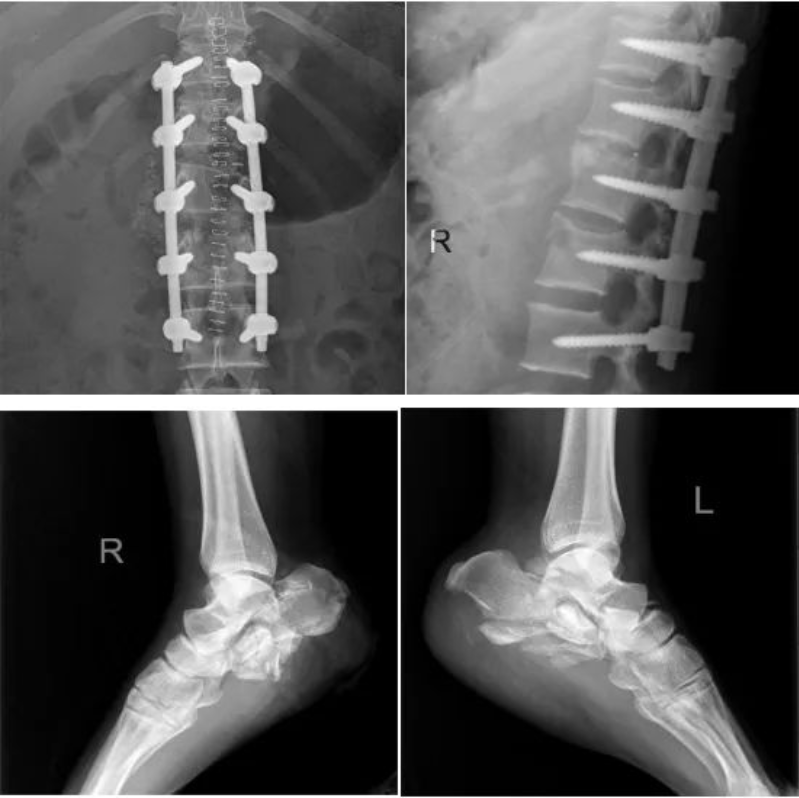

術后,經輸血等搶救治療谷女士生命體征及血色素水平逐漸平穩,但因早期失血過多導致嚴重休克,加上創傷所造成的肌肉橫紋肌溶解,其出現急性腎功能衰竭、無尿、身體出現水腫、高鉀血癥,病情危重!為恢復患者液體平衡,穩定內環境,謝煥坤主治醫生決定為患者上CRRT(連續性腎替代治療),但谷女士剛創傷術后不久,抗凝是個難題,為達到抗凝效果又減小出血風險,采用了最先進的局部枸櫞酸抗凝。同時為了能夠精細化容量管理,早期判斷心臟功能及肺水,凌晨兩點陳勁飛主任為其置入Picco導管,進行血流動力學監測,這一舉措為制定患者個體化液體治療方案起到了重要指導作用。經過Picco嚴密監測及CRRT治療,谷女士生命體征逐漸穩定并達到了液體平衡,順利脫離呼吸機拔除氣管插管,為下一步的手術創造了條件,于是重癥醫學科向脊柱外科姚仕奮主任發出會診邀請。姚仕奮為谷女士制定詳盡的手術計劃,其脊柱內固定手術進行很順利,術后愈合良好并轉出ICU。

文章配圖

谷女士創造了生命的奇跡,也凸顯多學科MDT聯合的創傷救治團隊的重要性。同時重癥醫護團隊精心的治療和優質的護理得到了谷女士及家屬的一致夸贊。谷女士目前病情穩定,骨折愈合良好,現處于肢體功能訓練康復階段,臉上終于露出了久違的笑容,直言要“爭取早日出院”。